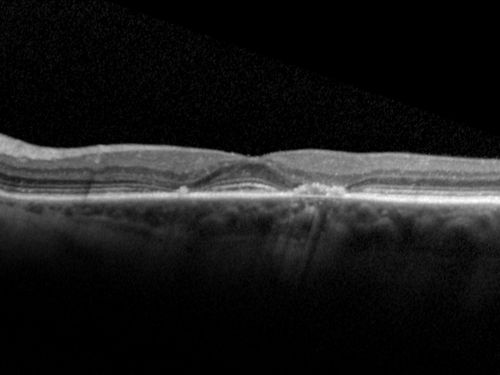

Plaquenil Toxicity both Eyes - Partial Bull's Eye - Discontinued 6 Years ago SD-OCT (Spectral domain optical coherence tomography)

82-year-old woman was on Plaquenil from 1976 from 2005, 200 mg a day.  It was discontinued because of abnormal visual fields 6 years ago. OD 20/32,  OS 20/40